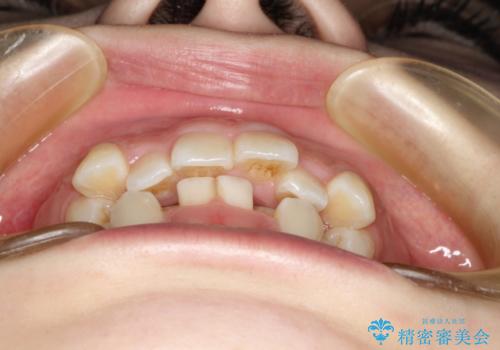

目立たない裏側矯正 抜歯矯正で口元を改善

- 前歯のデコボコと上顎の前突感による口の閉じにくさを気にして来院された患者様です。

目立たない装置を希望されたので、上顎が裏側装置のハーフリンガルを選択し、上下左右の小臼歯(計4歯)を抜歯して矯正治療を行うこととしました。